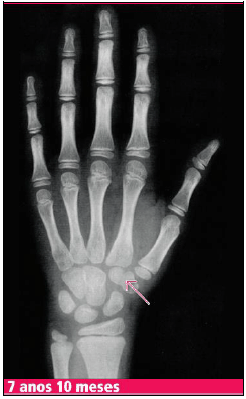

Paciente, sexo feminino, 5 anos e 3 meses, comparece à consulta por aparecimento de broto mamário. Mãe percebeu que nos últimos três meses houve crescimento de mamas. Refere que na escola é a criança mais alta da turma. Foi realizado Raio X de mãos e punhos para correlação da idade óssea com idade cronológica, com o seguinte resultado:

Enunciado 2606544-1

Qual o marco anatômico indicado para a identificação da idade óssea apresentada?